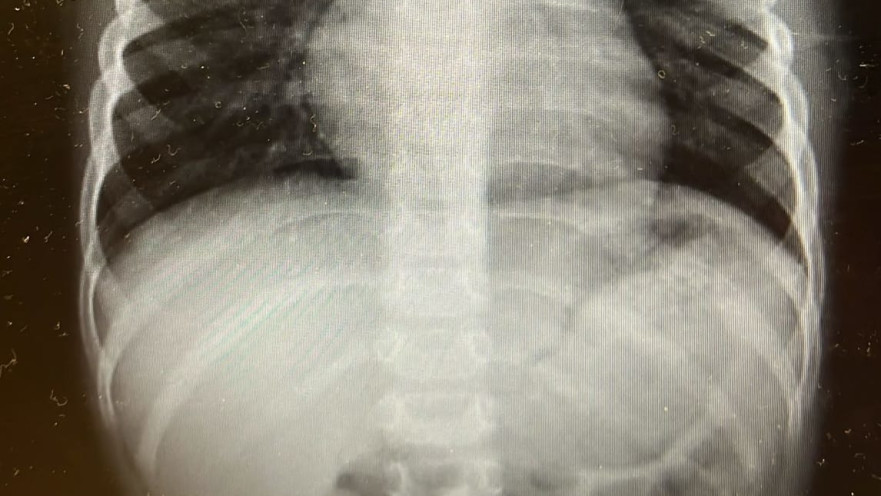

צילום רנטגן של בית החזה של הילד

צילום רנטגן של בית החזה של הילד | צילום: דוברות מרכז רפואי "מאיר" מקבוצת "כללית"

צילום רנטגן של בית החזה של הילד | צילום: דוברות מרכז רפואי ''מאיר'' מקבוצת ''כללית''

לדברי ד"ר זיפמן, "סוללה בוושט היא מצב חירום. מדובר באזור רגיש, שבו סוללות עלולות לגרום לנזק לרירית בתוך זמן קצר". הוא מסביר כי הפגיעה מתרחשת בשלושה מנגנונים: לחץ ישיר של הסוללה על הרירית, הפרשת חומרים קורוזיביים וזרם חשמלי הפוגע ברקמה. הרופאים במרכז רפואי מאיר מדגישים כי בכל חשד לבליעת סוללה – גם אם הילד נראה ללא תסמינים – יש להגיע מיד לבית החולים. ניתן למנוע מקרים כאלה באמצעות הקפדה על אבטחת הסוללות במוצרים והרחקתן מהישג ידם של ילדים.